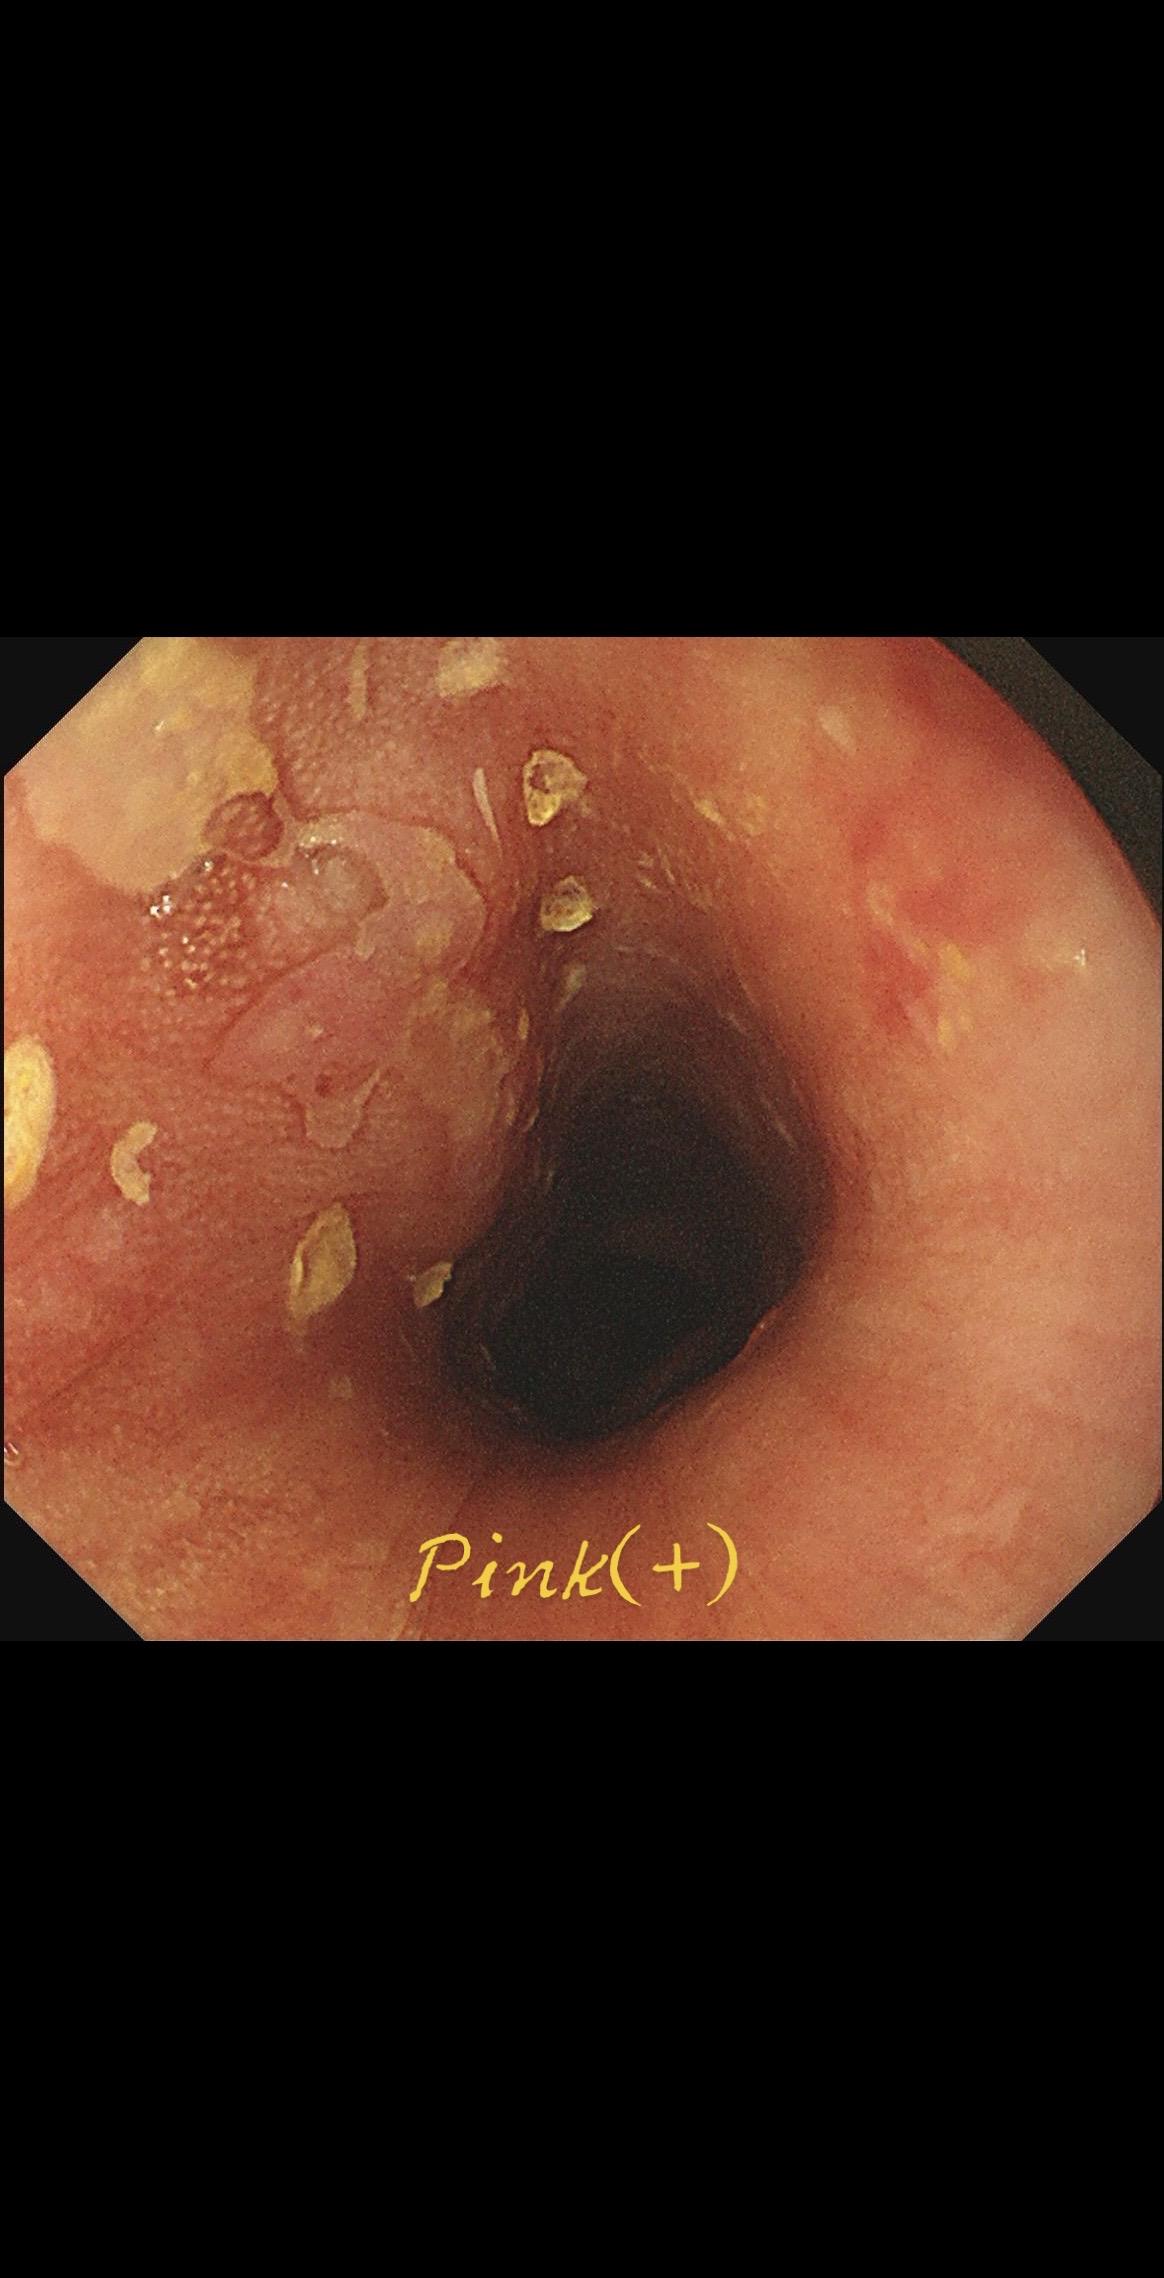

女,73岁,食管双发病变。泰州人,入院系统体检,首次胃镜检查,上段16-19cm见长条状病变,肛侧碘染局部不染;25cm处见一2mm粗糙潮红黏膜,浅凹陷,放大疑似R型不规则血管,卷发样改变,淡染,均行ESD切除。